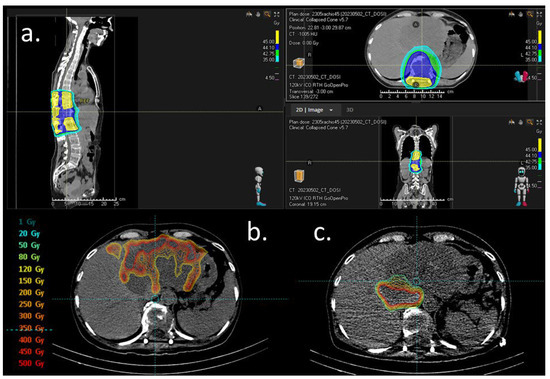

2. Case Presentation